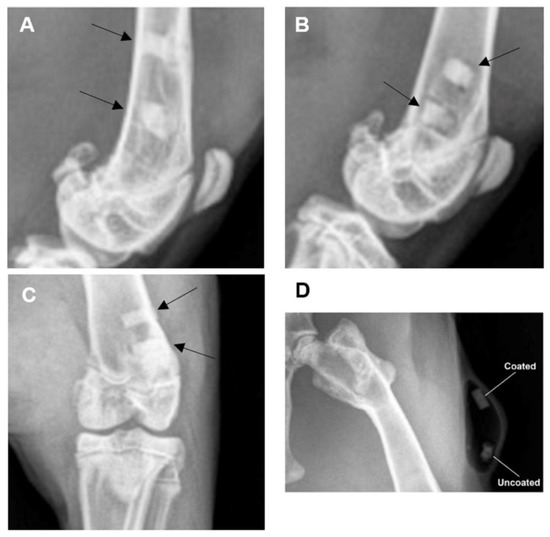

3.3.2. Radiographic Examination

3.3.3. Post-Mortem Examination Findings